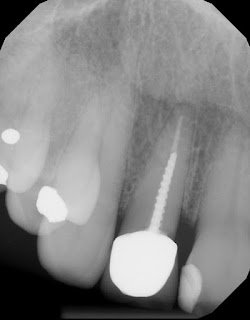

The endodontists at Superstition Springs Endodontics are skilled in restorative procedures closely associated with endodontic treatment. At your request, esthetic post and core buildups can be immediately placed following endodontic treatment.